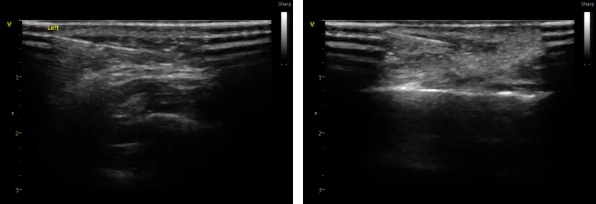

△ 超声引导下玻尿酸不同层次填充时呈像

一是精准避让血管,降低栓塞风险。超声可清晰呈现面部血管走向与位置,引导针尖避开危险区域,确保注射在安全层次开展,大幅降低血管栓塞等严重并发症概率。

二是分层精准注射,效果更自然。玻尿酸填充效果高度依赖注射层次,骨膜层、脂肪层、真皮层效果截然不同。超声能清晰区分组织层次,确保材料注入最佳解剖位置——如面部提升需打在骨膜层实现强支撑,可有效避免浅层注射导致的肿胀、僵硬、不自然。

三是实时监控分布,提升满意度。操作中医生可实时观察玻尿酸分布,避免局部堆积、凹凸不平,同时结合软组织评估,为求美者定制个性化方案,兼顾安全与美观,让变美过程更可控、更放心。